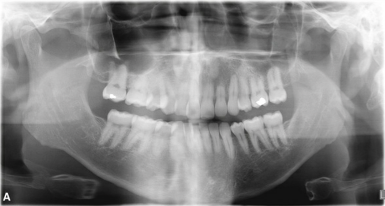

What is this positioning error?

Teeth in front of focal trough

- Artefact where anterior teeth or the hall arch is placed in front of the focal trough so you can see a lot of narrowing of teeth & a lot of spine is visible – should only be able to see anterior aspect of spine not entire spine

- When structures are in front of focal trough they look narrower